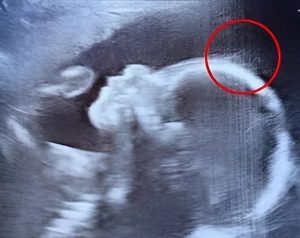

The sonographer paused for a moment during the ultrasound, tilting her head slightly before breaking into a grin. “Wait a minute. Is that hair?” she asked. Emily laughed nervously. Another doctor entered the room, examined the screen, and joked, “Looks like you’ve got a little rock star growing in there. She might skip the bald baby phase altogether.”

Sure enough, there on the monitor, delicate wisps floated like underwater ribbons—visible strands of hair swaying gently in the amniotic fluid. It wasn’t a common sight at this stage of pregnancy, and the medical team was fascinated.

In Ivy’s case, the hair wasn’t just visible on the scan. It was long, thick, and remarkably well-developed. The medical team had never witnessed anything quite like it during a routine scan, and everyone in the room shared in Emily’s astonishment and joy.